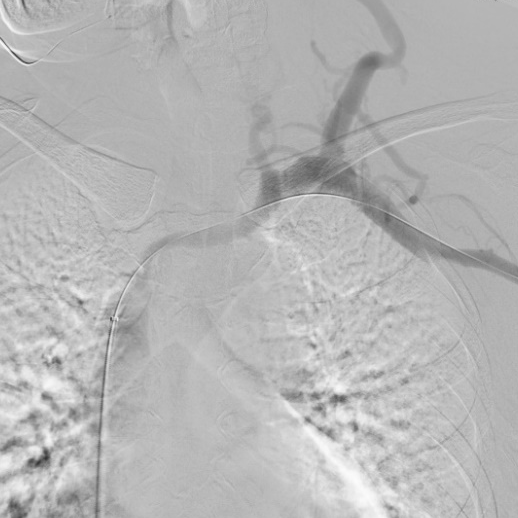

【病例分享】郭明金教授团队:Venovo静脉支架在左头臂静脉闭塞病变中应用

诊断:1、左头臂静脉闭塞,2、慢性肾衰竭尿毒症期,3、高血压。